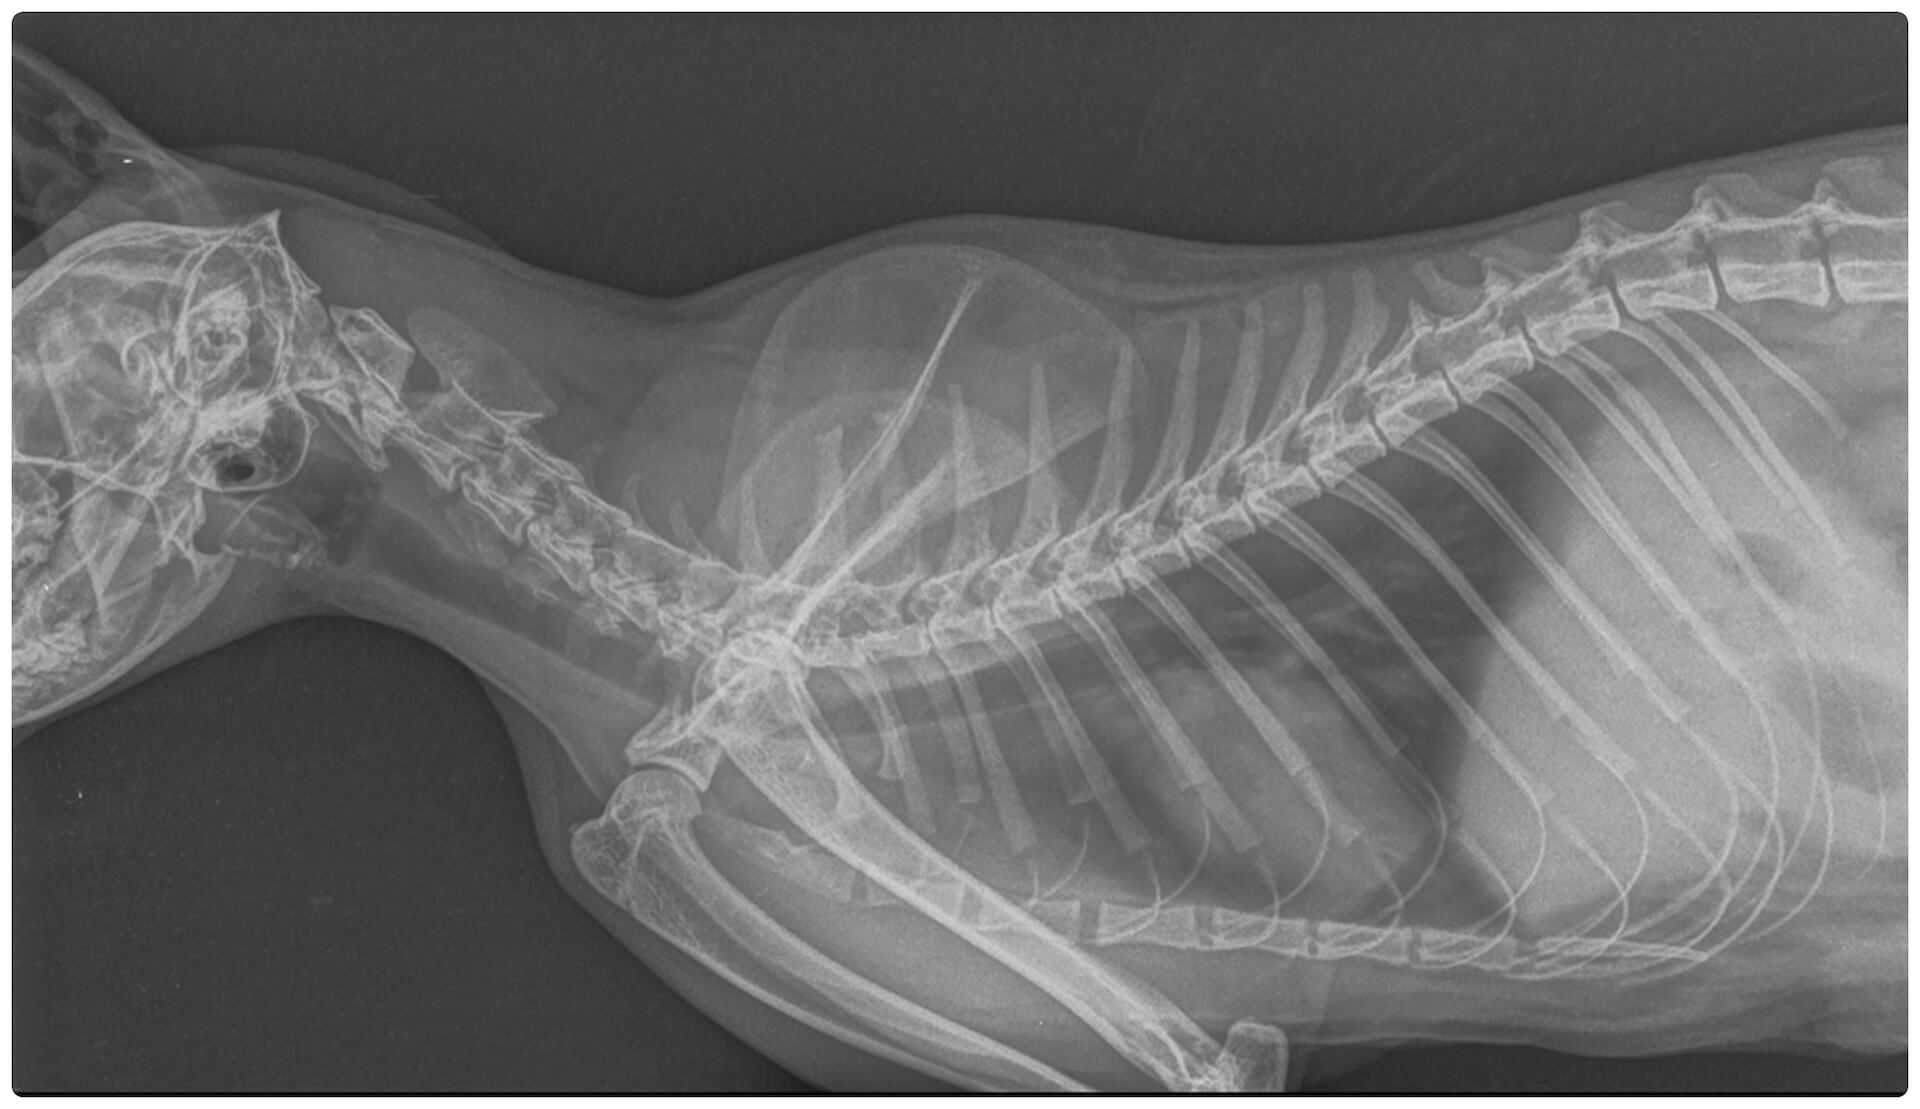

Radiography (X-ray imaging) is the most common diagnostic imaging procedure used in veterinary practices. It produces black, white, and gray images (radiographs) of bones, foreign objects, and large body cavities. Radiography is particularly useful for detecting fractures, tumors, injuries, infections, and deformities. In some cases, specialized X-ray techniques called contrast procedures are used to provide more detailed images of body organs.